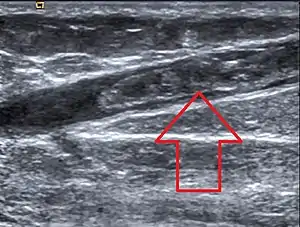

| Greater saphenous vein thrombosis |

SVTs may be diagnosed based upon clinical criteria by a healthcare professional.[1] A more specific evaluation can be made by ultrasound.[1] An ultrasound can be useful in situations in which an SVT occurs above the knee and is not associated with a varicose vein, because ultrasounds can detect more serious clots like DVTs.[2] The diagnostic utility of D-dimer testing in the setting of SVTs has yet to be fully established.[3]